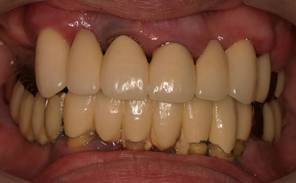

術後。上部構造はハイブリッドレジンです。しっかり嚙めるようになり喜んでいただきました。

上部構造装着後6年。ハイブリッドレジンを使用したため、少し艶がなくなってきました。上部構造の材料には金属、ハイブリッドレジン、セラミックなどがあります。セラミックはきれいですが欠けやすいため、最近はフルジルコニアを使っています。